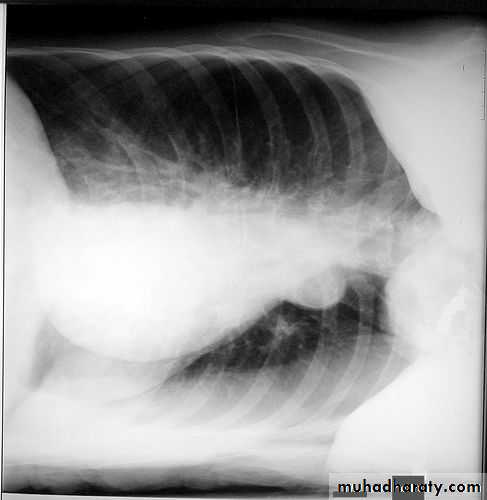

2- lateral.

Lateral view position